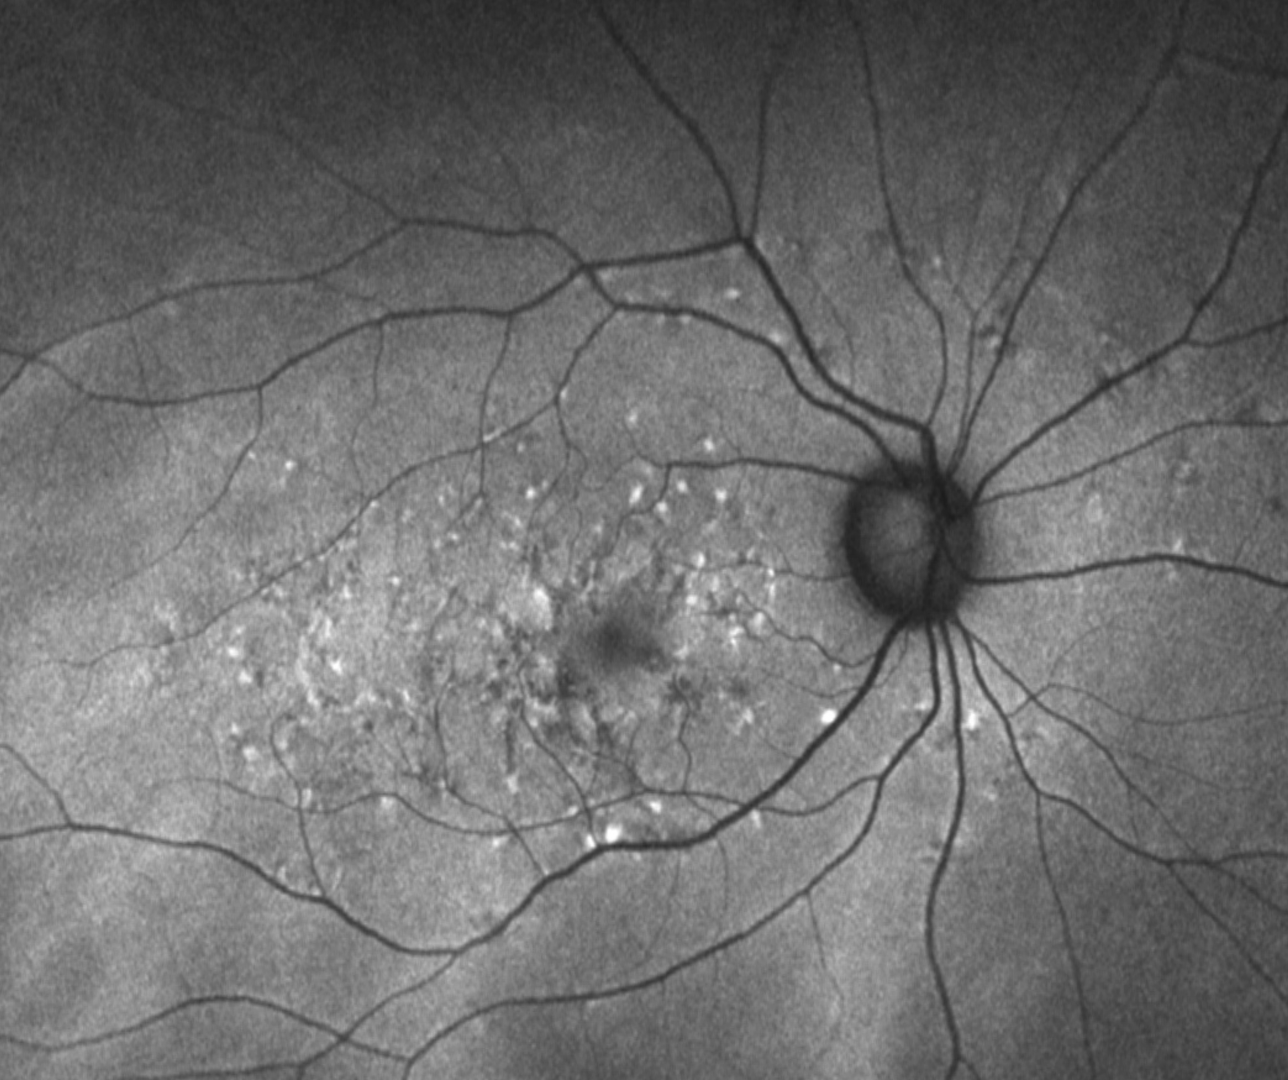

Pattern dystrophies constitute a group of clinically and genetically heterogeneous retinal disorders characterised by a variety of deposits of yellow, orange, or dark pigment, predominantly in the macular area. The age of onset can be quite variable but usually around the 3rd to 5th decade. It is typically slowly progressive with a relatively good visual prognosis, although vision loss can occur as a result of macular atrophy and/or the development of choroidal neovascularisation.

There are five types of pattern dystrophy categorized on the pigment distribution.

1. Adult-onset foveomacular vitelliform dystrophy

2. Butterfly shaped pigment dystrophy

3. Reticular dystrophy of the RPE

4. Multifocal pattern dystrophy simulating Stargardt disease

5. Fundus pulverulentus